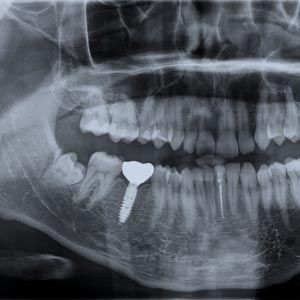

If you have suffered jaw recession, you may need a bone graft or sinus lift before implant placement. Additional procedures will add to the overall cost of rehabilitating your smile.